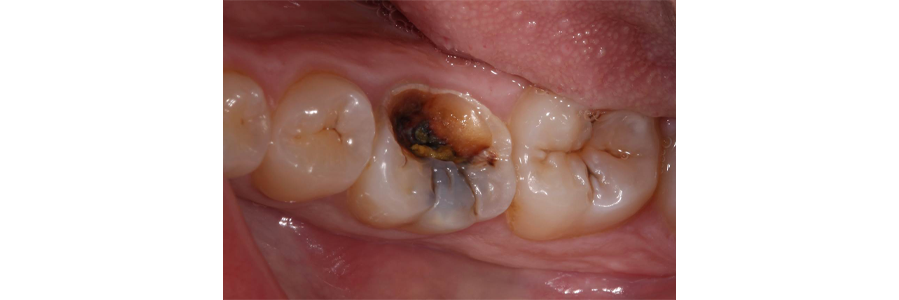

In this case study, tooth #19 had a large carious lesion and tested vital prior to caries excavation (Fig. 1).